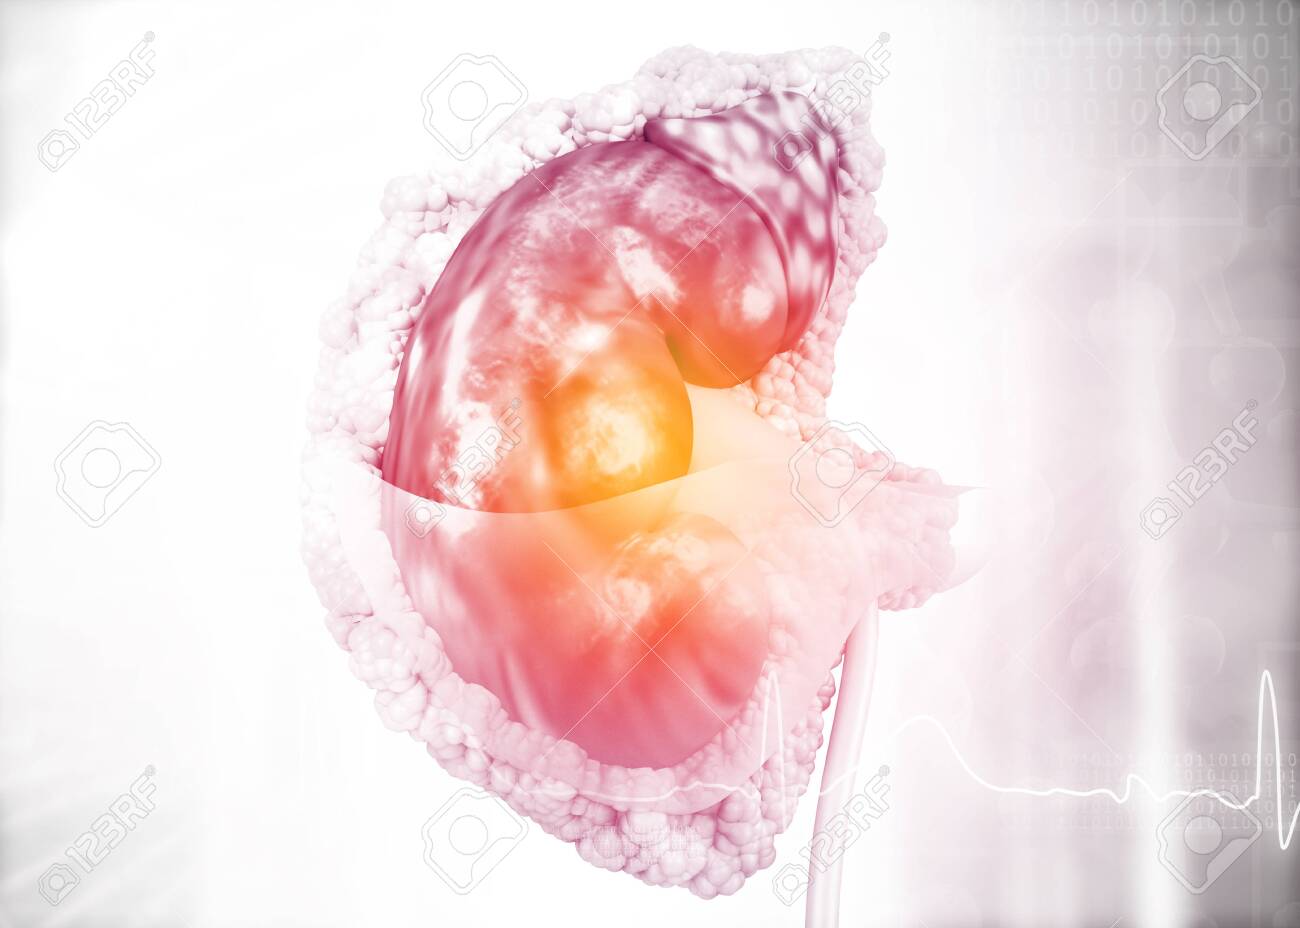

3d, adrenal, anatomy, arteries, background, biology, blood cell, body, cancer, care details, colour, diagram, dialysis, digestive, disease, education, gland, health, human, illustration, inside, internal, kidney, medical, medicine, organ, physiology, renal, render, science, section, stones, study, system, threedimensional, transplant, ureter, urinary, vessel,